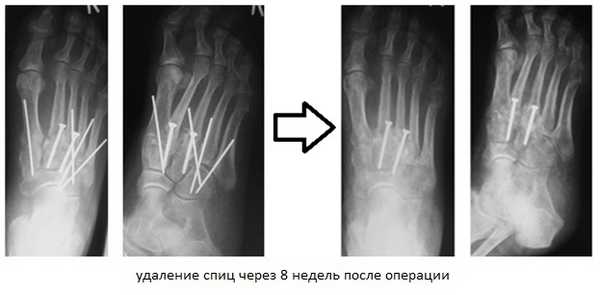

При смещении более 2 мм, нестабильности при функциональных тестах – рекомендовано открытое устранение вывиха с жёсткой фиксацией винтами или пластинами. Используются один или два продольных доступа в 1 и 2 межплюсневых промежутках. После обнажения первого предплюсне-плюсневого сустава первым этапом устраняется межклиновидная нестабильность, вторым этапом устраняется предплюсне-плюсневая нестабильность. В послеоперационном периоде сразу начинается разработка активного объёма движений. Нагрузку на стопу начинают постепенно, с тем чтобы полностью её восстановить к 6-8 неделе. Удаление спиц Киршнера производится через 6-8 недель, компрессирующих винтов через 3-6 месяцев. Возвращение к полной физической активности не ранее 9-12 месяцев после операции.

В ряде случаев целесообразно применить смесь хирургических техник. Если рассматривать весь сустав Лисфранка разбив на внутренний, центральный и наружный отделы, то его внутренний (1) и латеральный (4-5) отделы подвижны, хотя и с малой амплитудой, а центральный (2-3) практически не подвижен. По этой причине в хирургической практике часто используется неполный артродез, то есть выполняют артродез 2-3 предплюсне-плюсневых суставов а 1,4,5 временно фиксируют спицами.

![вывих стопы]()

Это позволяет сохранить нормальную биомеханику стопы и предотвратить раннее развитие артроза в смежных суставах которое характерно для полного артродеза.